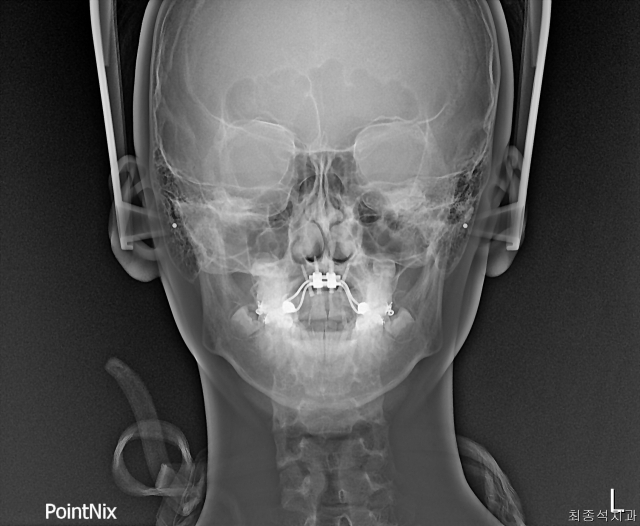

위 두 장은 같은 환자의 시술 전후 얼굴 엑스레이 사진. 입천장이 넓어지면서 비강(콧속)에 공기가 지나는 기도도 확장된 게 보인다. 최종석치과의원 제공 위 두 장은 같은 환자의 시술 전후 얼굴 엑스레이 사진. 입천장이 넓어지면서 비강(콧속)에 공기가 지나는 기도도 확장된 게 보인다. 최종석치과의원 제공